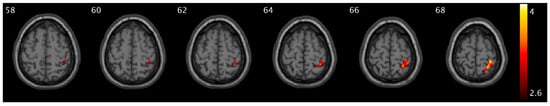

We observed significant group and urge interaction effects for CBF and PCC FC (Figure 1). Compared to healthy controls, OAB participants demonstrated significant decreases in ΔCBF (from low to high urge) in the medial prefrontal region, specifically in the superior frontal and superior medial frontal areas (Figure 1A). There were significant increases in ΔCBF (from low to high urge state) in the cuneus, supramarginal extending to inferior parietal, middle, and superior temporal regions (Figure 1B). There were significant decreases in ΔPCC FC (from low to high urge) in the insula, putamen, and pallidum regions (Figure 1C). A summary of the clusters’ statistics is reported in Table S1.

Figure 1. Statistical maps overlaid on T1-weighted images showing group and urge interaction effects. (A) Decreases in ΔCBF (from low- to high-urge state) in the superior frontal and superior medial frontal regions; (B) increases in ΔCBF in the cuneus, supramarginal extending to inferior parietal, middle, and superior temporal regions; (C) decreases in ΔPCC FC in the insula, putamen, and pallidum regions in OAB participants compared to healthy controls. The numbers in the top left corner of the MRI images indicate the z-coordinate (in mm) in the MNI space. The color bars represent t-values.